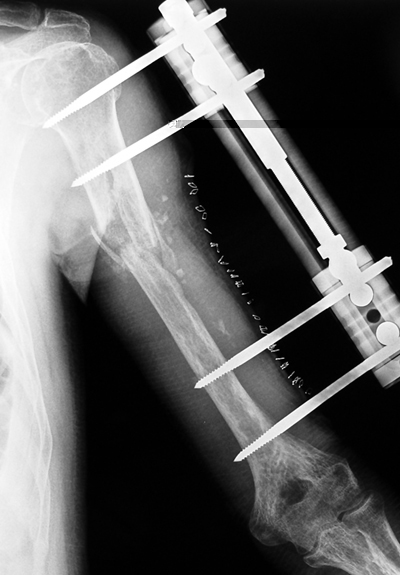

Psödartroz tedavisinde alt ekstremitede kaynama elde edilmesinin yanında kemik boylarının da eşitlenmesi amaçlanır. Buna karşın humerus diafiz psödartrozlarının tedavisinde 4-5 cm’ ye kadar olan ekstremite uzunluk farkları kabul edilebilir sınırlardadır; fonksiyonel ve kozmetik yönlerden morbidite oluşturmaz. Ring ve ark. defektleri kortikospongiöz otogreft ve dinamik kompresyon plağı ile köprülemişlerdir. Buna karşın defekt rekonstruksiyonunun hastaların fonksiyonlarına istatistiksel açıdan anlamlı bir etkisi olduğuna değinmemişlerdir.Ortalama 2.4 (1-5) cm tespit edilen kısalığın fonksiyonlarını ve kozmetik görünümlerini etkilemediği görüldü. Bu nedenle 5 cm’ ye kadar olan defektlerde monofokal girişim yapılmasının hem tedavi süresini hem de sonucunu olumlu yönde etkileyeceğini düşünmekteyiz. Buna karşın 6 cm ve üzerindeki defektlerde bifokal kompresyon distraksiyon uygulaması ile humerus uzunluğunun da restorasyonu sağlanabilir. Gür ve ark. humerus psödartroz tanısı ile İlizarov sirküler eksternal fiksatör uyguladıkları 9 olgunun sekizinde kaynama sağlamışlar, konvansiyonel metodlarla tedavi ettikleri humerus psödartrozlarında sıkça gördükleri dirsek ve omuz eklem hareketlerindeki kısıtlılıkları görmediklerini, yöntemin güvenli ve etkili olduğunu vurgulamışlardır. Lammens ve ark. altısı enfekte 30 humerus psödartrozu olgusunu İlizarov eksternal fiksatör ile tedavi etmişler, 28 olguda (% 93.3) ortalama 4.5 ayda kaynama sağlamışlardır. İlizarov eksternal fiksatörü ile sağlanan güçlü fiksasyonun daha iyi fonksiyon ve kabul edilebilir süreler içinde önemli komplikasyon yaşanmaksızın solid kaynama sağladığını bildirmişlerdir. Çerçeve çıkarıldıktan sonra 4 olguda refraktür gelişmiş ve İlizarov eksternal fiksatör sistemini tekrar uygulamaları gerekmiştir.

Yöntemin dezavantajlarından çerçevenin ağır olması karbon halkaların kullanılması ile azaltılabilir. Tedavi edilen hastalarda karbon halkalar kullanıldı. Böylece hasta daha konforlu olurken, radyolojik kontrollerde de kaynama çok daha iyi gözlendi. Eksternal fiksasyon uygulamalarında sıkça karşılaşılan tel-çivi yolu enfeksiyonları, uygun uygulama teknikleri ve titiz çivi dibi bakımı ile azaltılabilir. Sonuç olarak ortopedik cerrahlar için her zaman zor ve sorunlu olan humerus psödartrozlarının tedavisinde Ilizarov yöntemi klasik yöntemlere birçok üstünlükler sağlamaktadır. Tedavinin birinci gününden itibaren kişinin fonksiyonel hale gelebildiği, tedavi süresince “cerrahın ellerinin her zaman kırığa hakim olmasını sağlayan” Ilizarov eksternal fiksatör uygulamasının klasik humerus psödartrozlarında, kısa kaynama süresi ve düşük komplikasyon oranları ile, daha invazif klasik yöntemlere önemli bir alternatif oluşturduğu, ayrıca deformite, enfeksiyon, defekt varlığı, kısalık ya da eklem hareket kısıtlılıklarının eşlik ettiği sorunlu humerus psödartrozlarında ise alternatifsiz bir tedavi yöntemi olduğu kanısındayız.